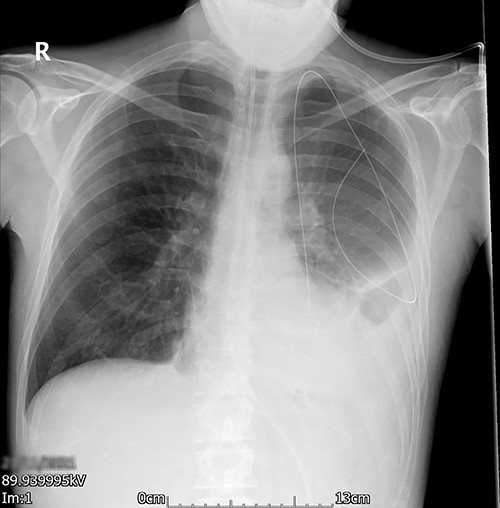

A young adult with a past medical history of asthma, depression and high alcohol intake was admitted with coronavirus (COVID) pneumonitis and type 2 respiratory failure. During his admission to the local hospital, he developed a left-sided pleural effusion. After confirming the diagnosis by a CT scan, an 18 French gauge (Fr) chest drain was inserted by the Seldinger technique (Fig. 1). The never event of a retained foreign body intrapleural was brought to light at the post-procedure X-ray (Fig. 2). The X-ray showed the retention of the guidewire in the thoracic cavity. The patient was referred to us for urgent retrieval of the guidewire. The patient was transferred, and a course of intravenous antibiotics for 10 days was completed, as per the advice of the infectious diseases colleagues; once the infection parameters were normal and the patient was COVID-19 negative, he underwent a left-sided video-assisted thoracoscopic surgery (VATS) for removal of the foreign body.

Posterior–anterior chest radiograph after chest drain insertion showing the retained guidewire in the left pleural cavity. In addition, left pleural effusion can be noted.